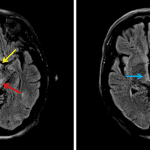

- T2/FLAIR signal hyperintensity in the bilateral periaqueductal gray matter, medial thalami, hypothalamus, and possibly mamillary bodies

- Scattered T2/FLAIR hyperintensities in the periventricular and subcortical white matter

- Extraaxial lesion along the lateral aspect of the right temporal lobe with low signal on all sequences

- Wernicke encephalopathy

T2/FLAIR signal hyperintensity in the bilateral periaqueductal gray matter, medial thalami, hypothalamus, and possibly mamillary bodies. Though nonspecific, this distribution of signal abnormality raises particular concern for Wernicke encephalopathy. No evidence of acute ischemia.

Scattered T2/FLAIR hyperintensities in the periventricular and subcortical white matter, which though nonspecific are commonly attributable to chronic small vessel disease.

Extraaxial lesion along the lateral aspect of the right temporal lobe with low signal on all sequences, likely representing bulky dystrophic calcification. Consider postcontrast imaging to assess for associated enhancing mass.